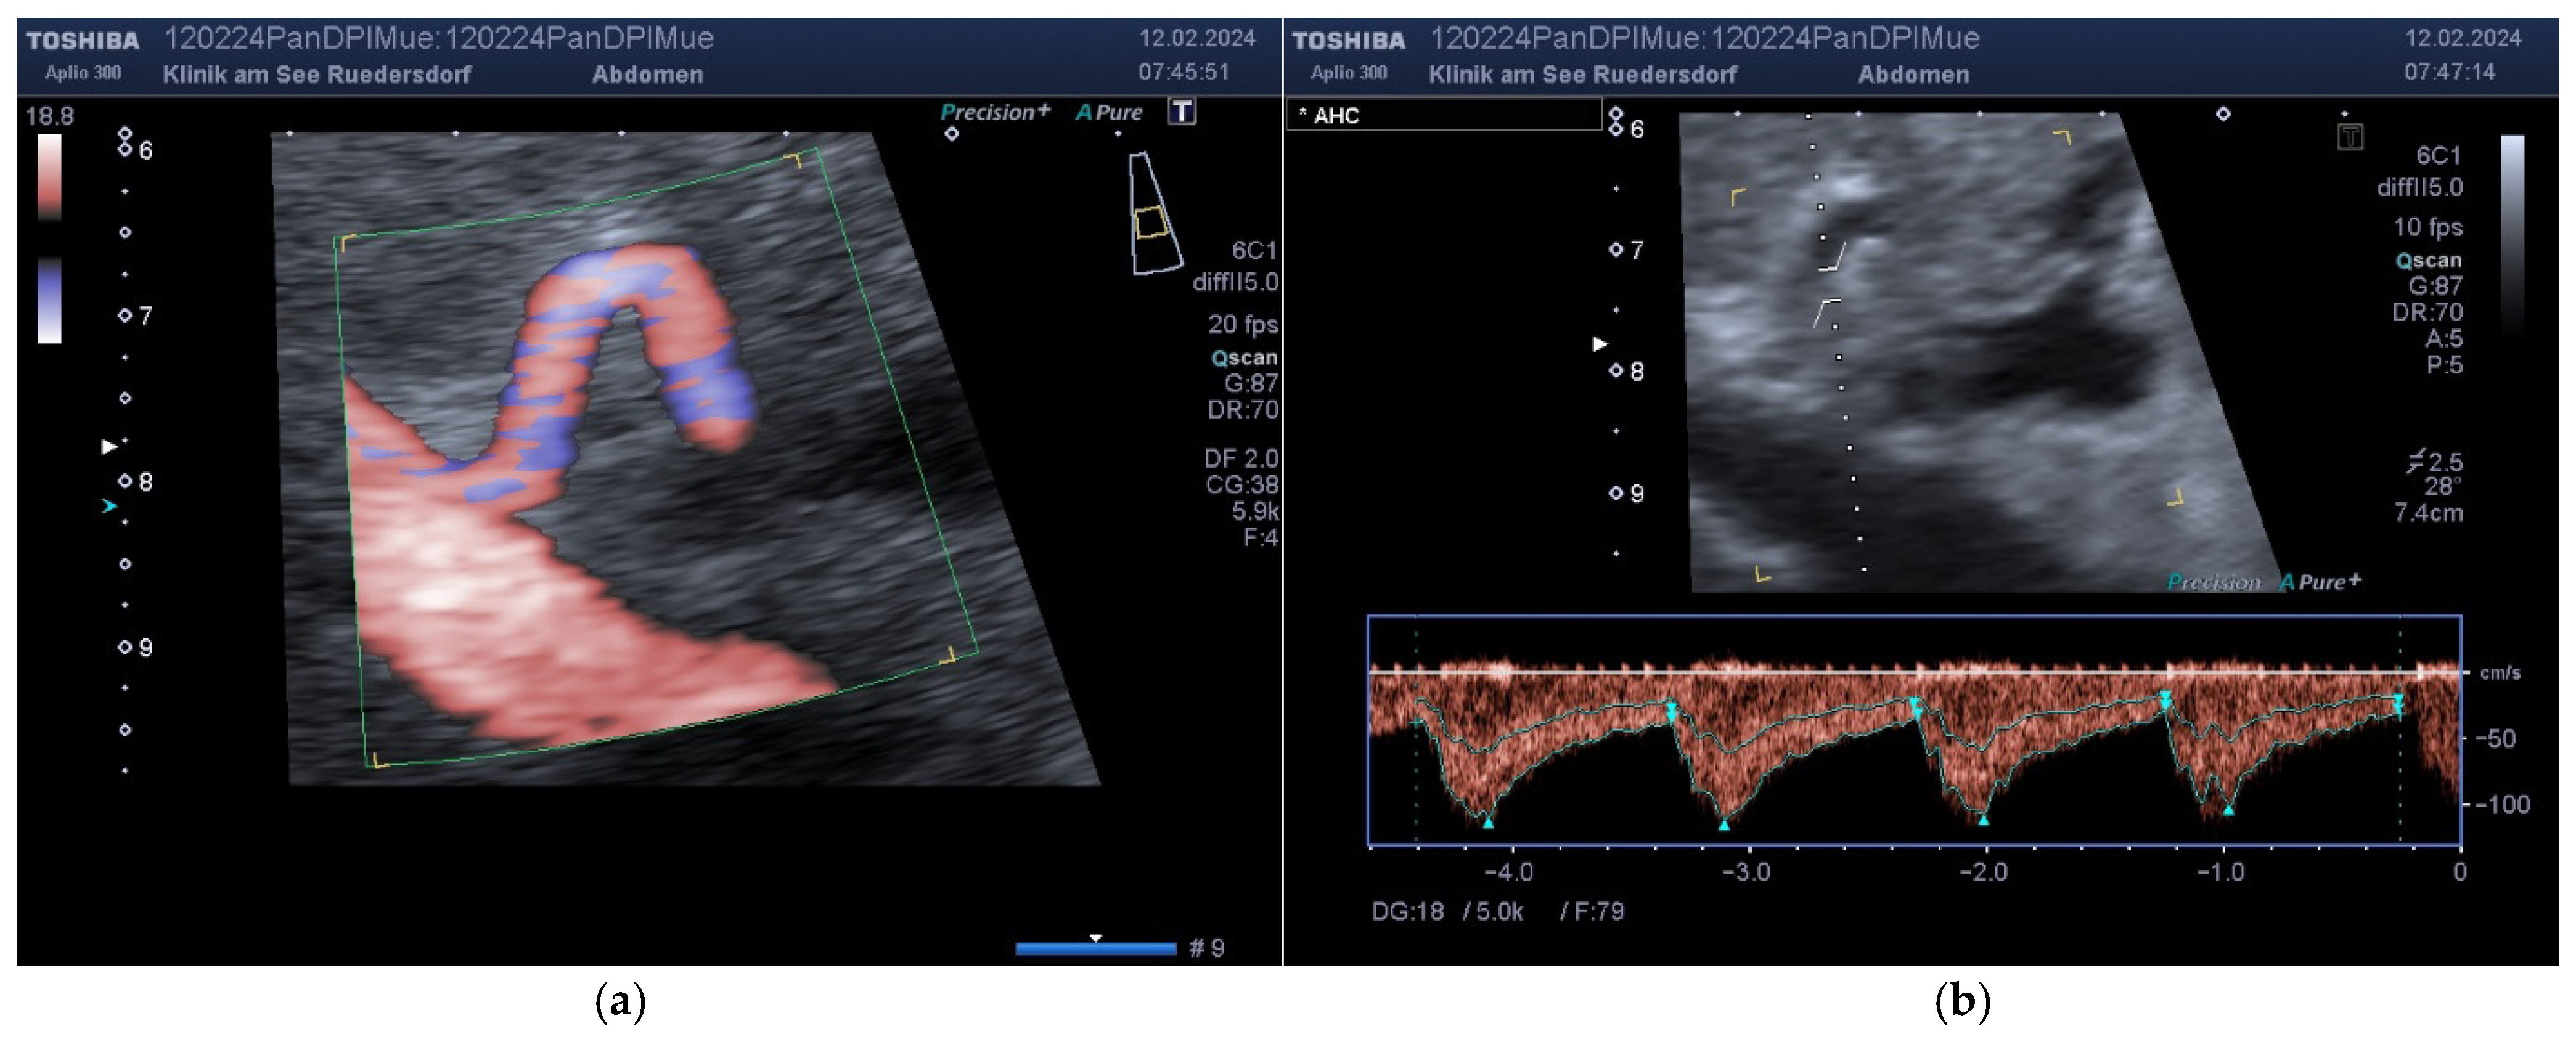

2.3.1. Determination of Vessel Diameter

2.3.2. Location of the Probe, Insonation Angle, and Doppler Window

3.2. Measured Values and Calculated Blood Flow